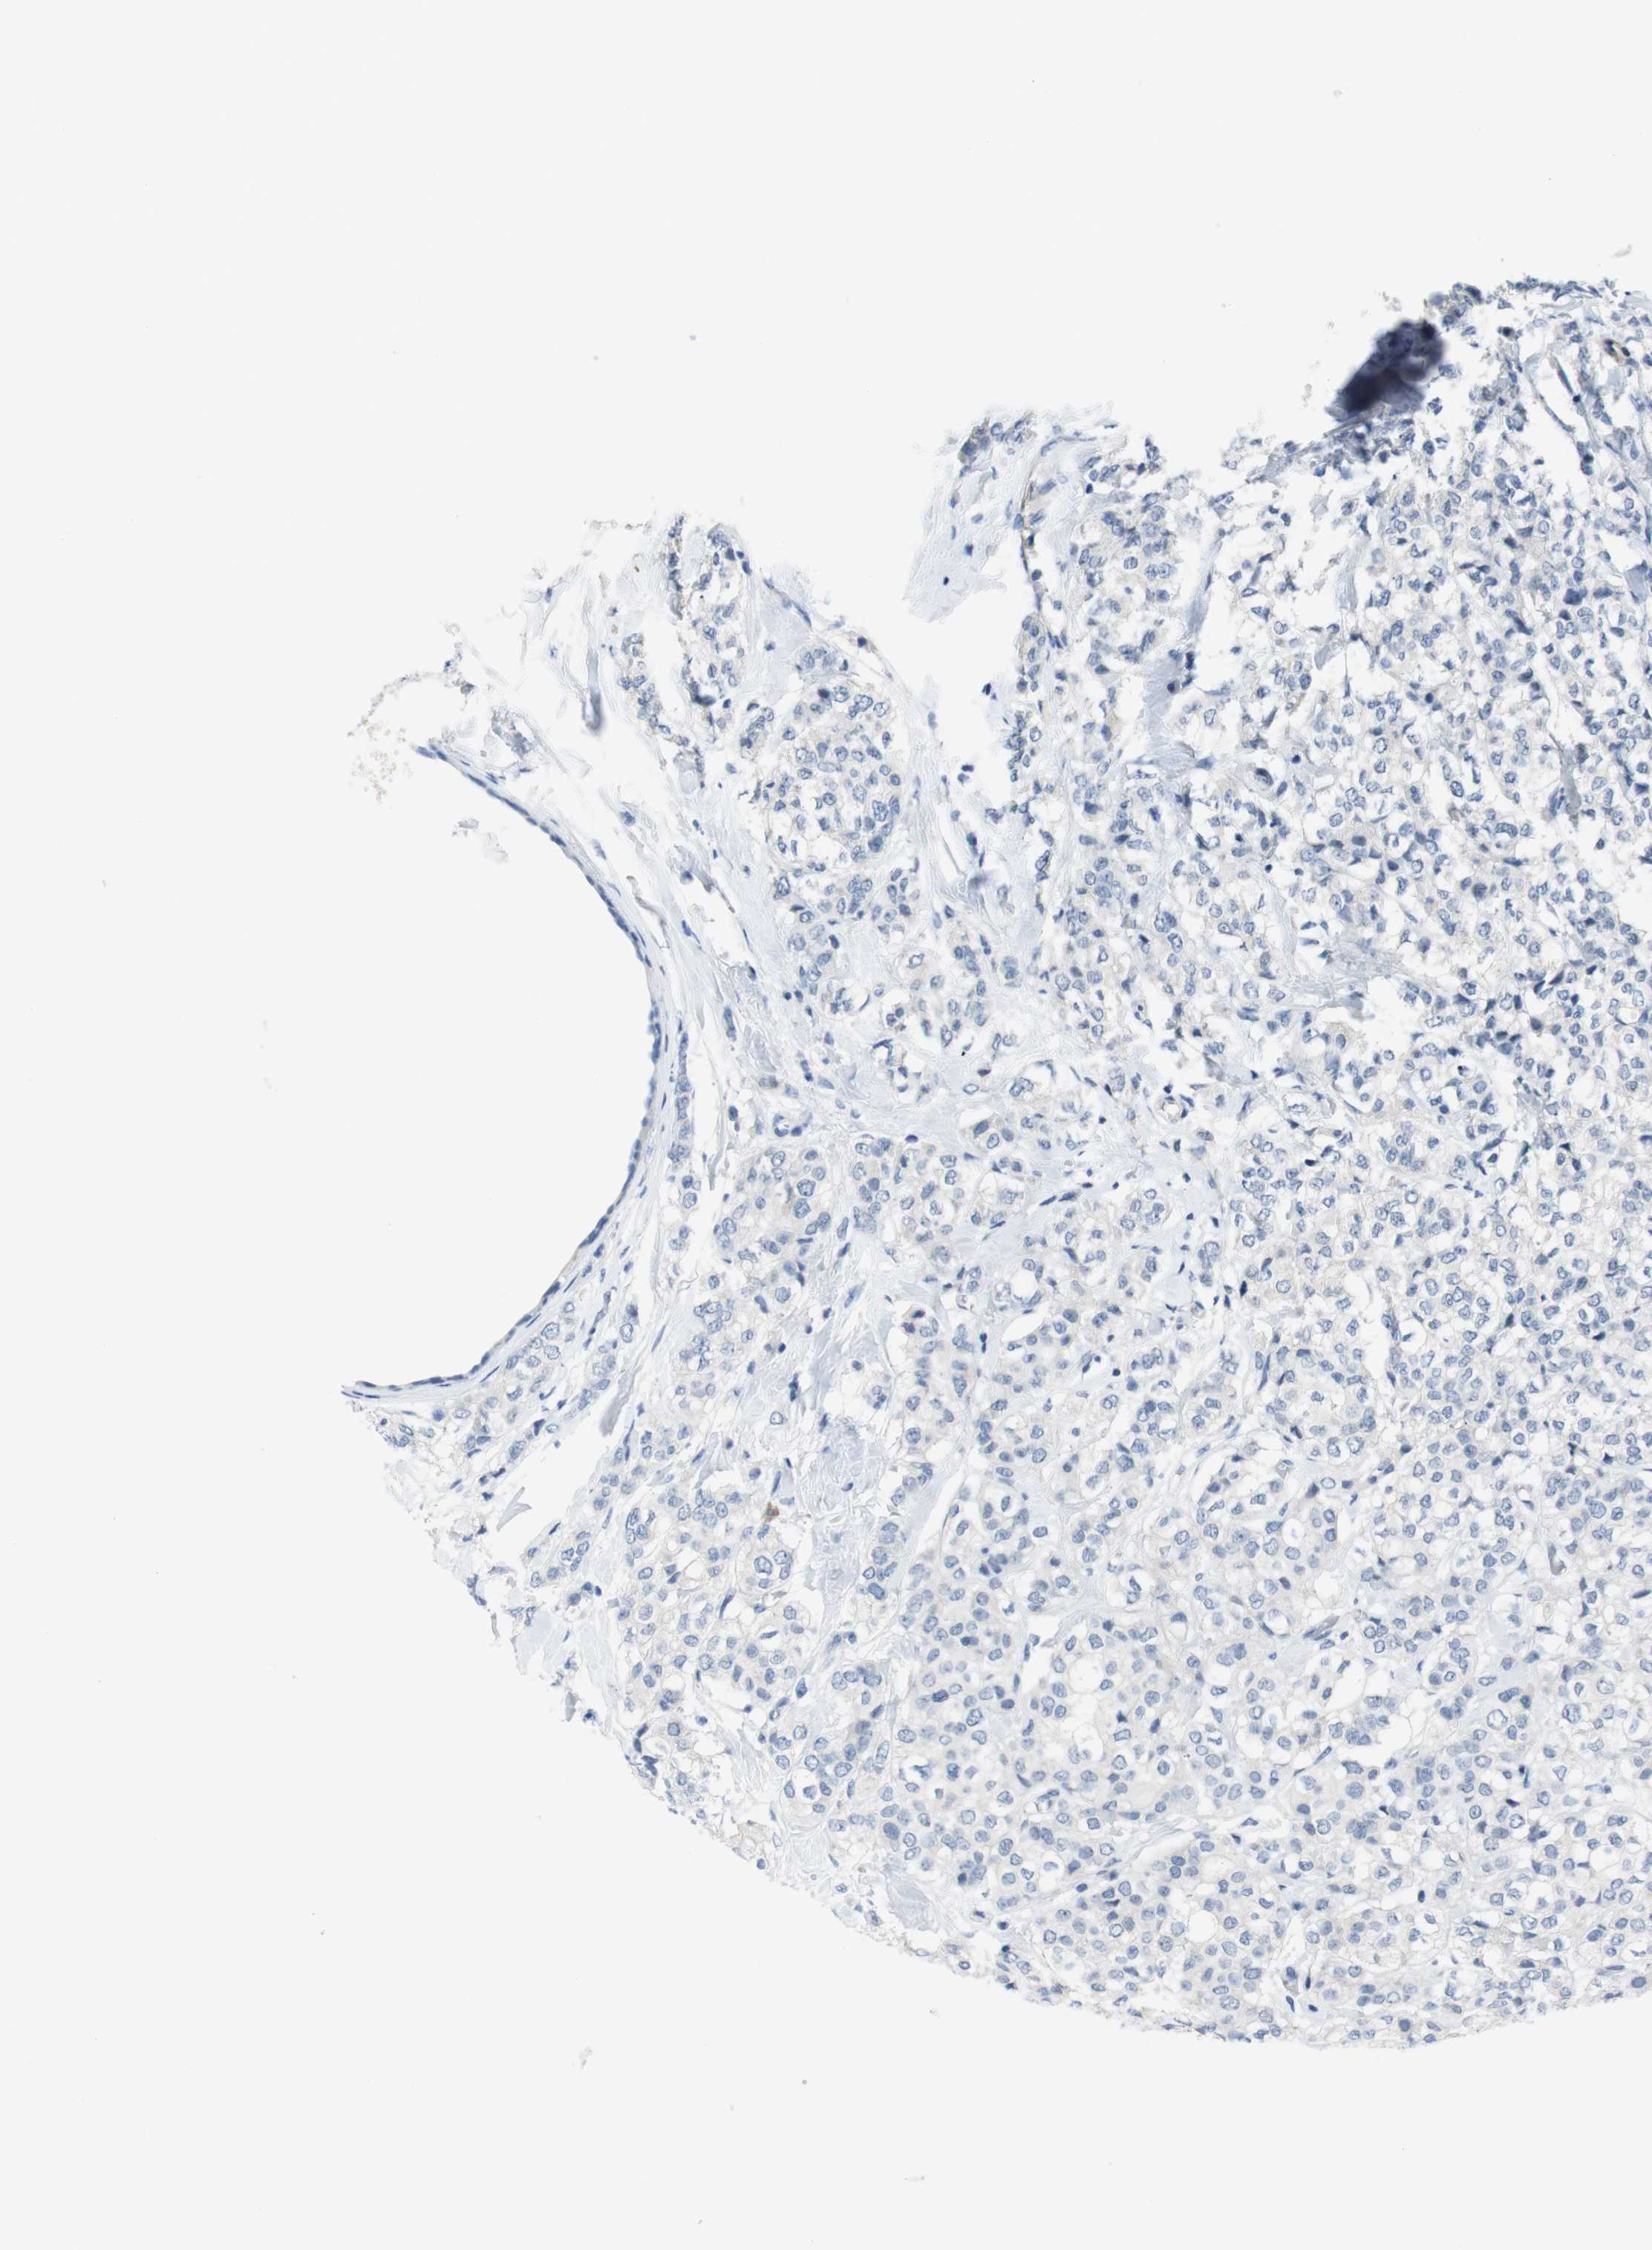

BRCA TCGA BRCA VALIDATION PROTEIN EXPRESSION

ANTIBODIES

AND

VALIDATION